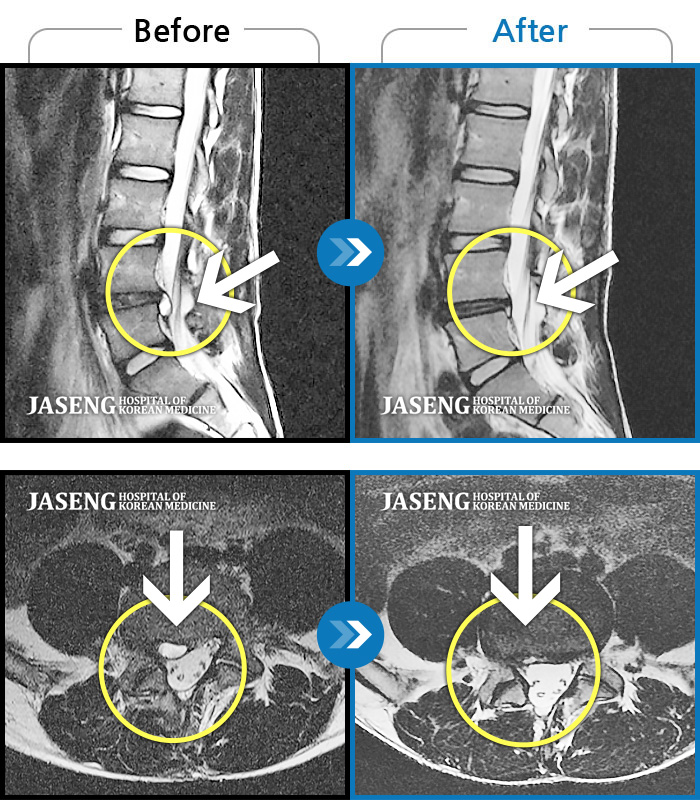

지난 10월 15일 부터 2주간 입원치료와 원장님을 믿고 따라간 통원치료 3주간의 여정이 이제 끝났습니다. 당시 디스크1~2번이 터지고, 3~4번에 염증이 많아 송내자생한방병원에 실려 갔었지요. 입원당일 얼마나 고통이 심했던지 오죽하면 혼절까지 했을까요.....저 때문에 6층 병동 간호사실에 비상이 걸렸지요. 그런 저를 침치료와 한약처방만으로 일으켜 세웠으니, 원장님은 정말 대단하십니다. 명의 중 명의이십니다.